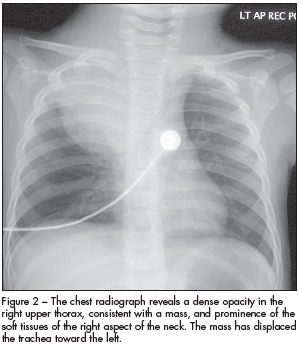

DISCUSSION: In addition to the lateral neck mass, physicians in the emergency department noted dilated superficial vessels on the right anterior chest wall (Figure 1). A chest radiograph demonstrated a large density in the right upper lobe with a mediastinal shift to the left side (Figure 2).